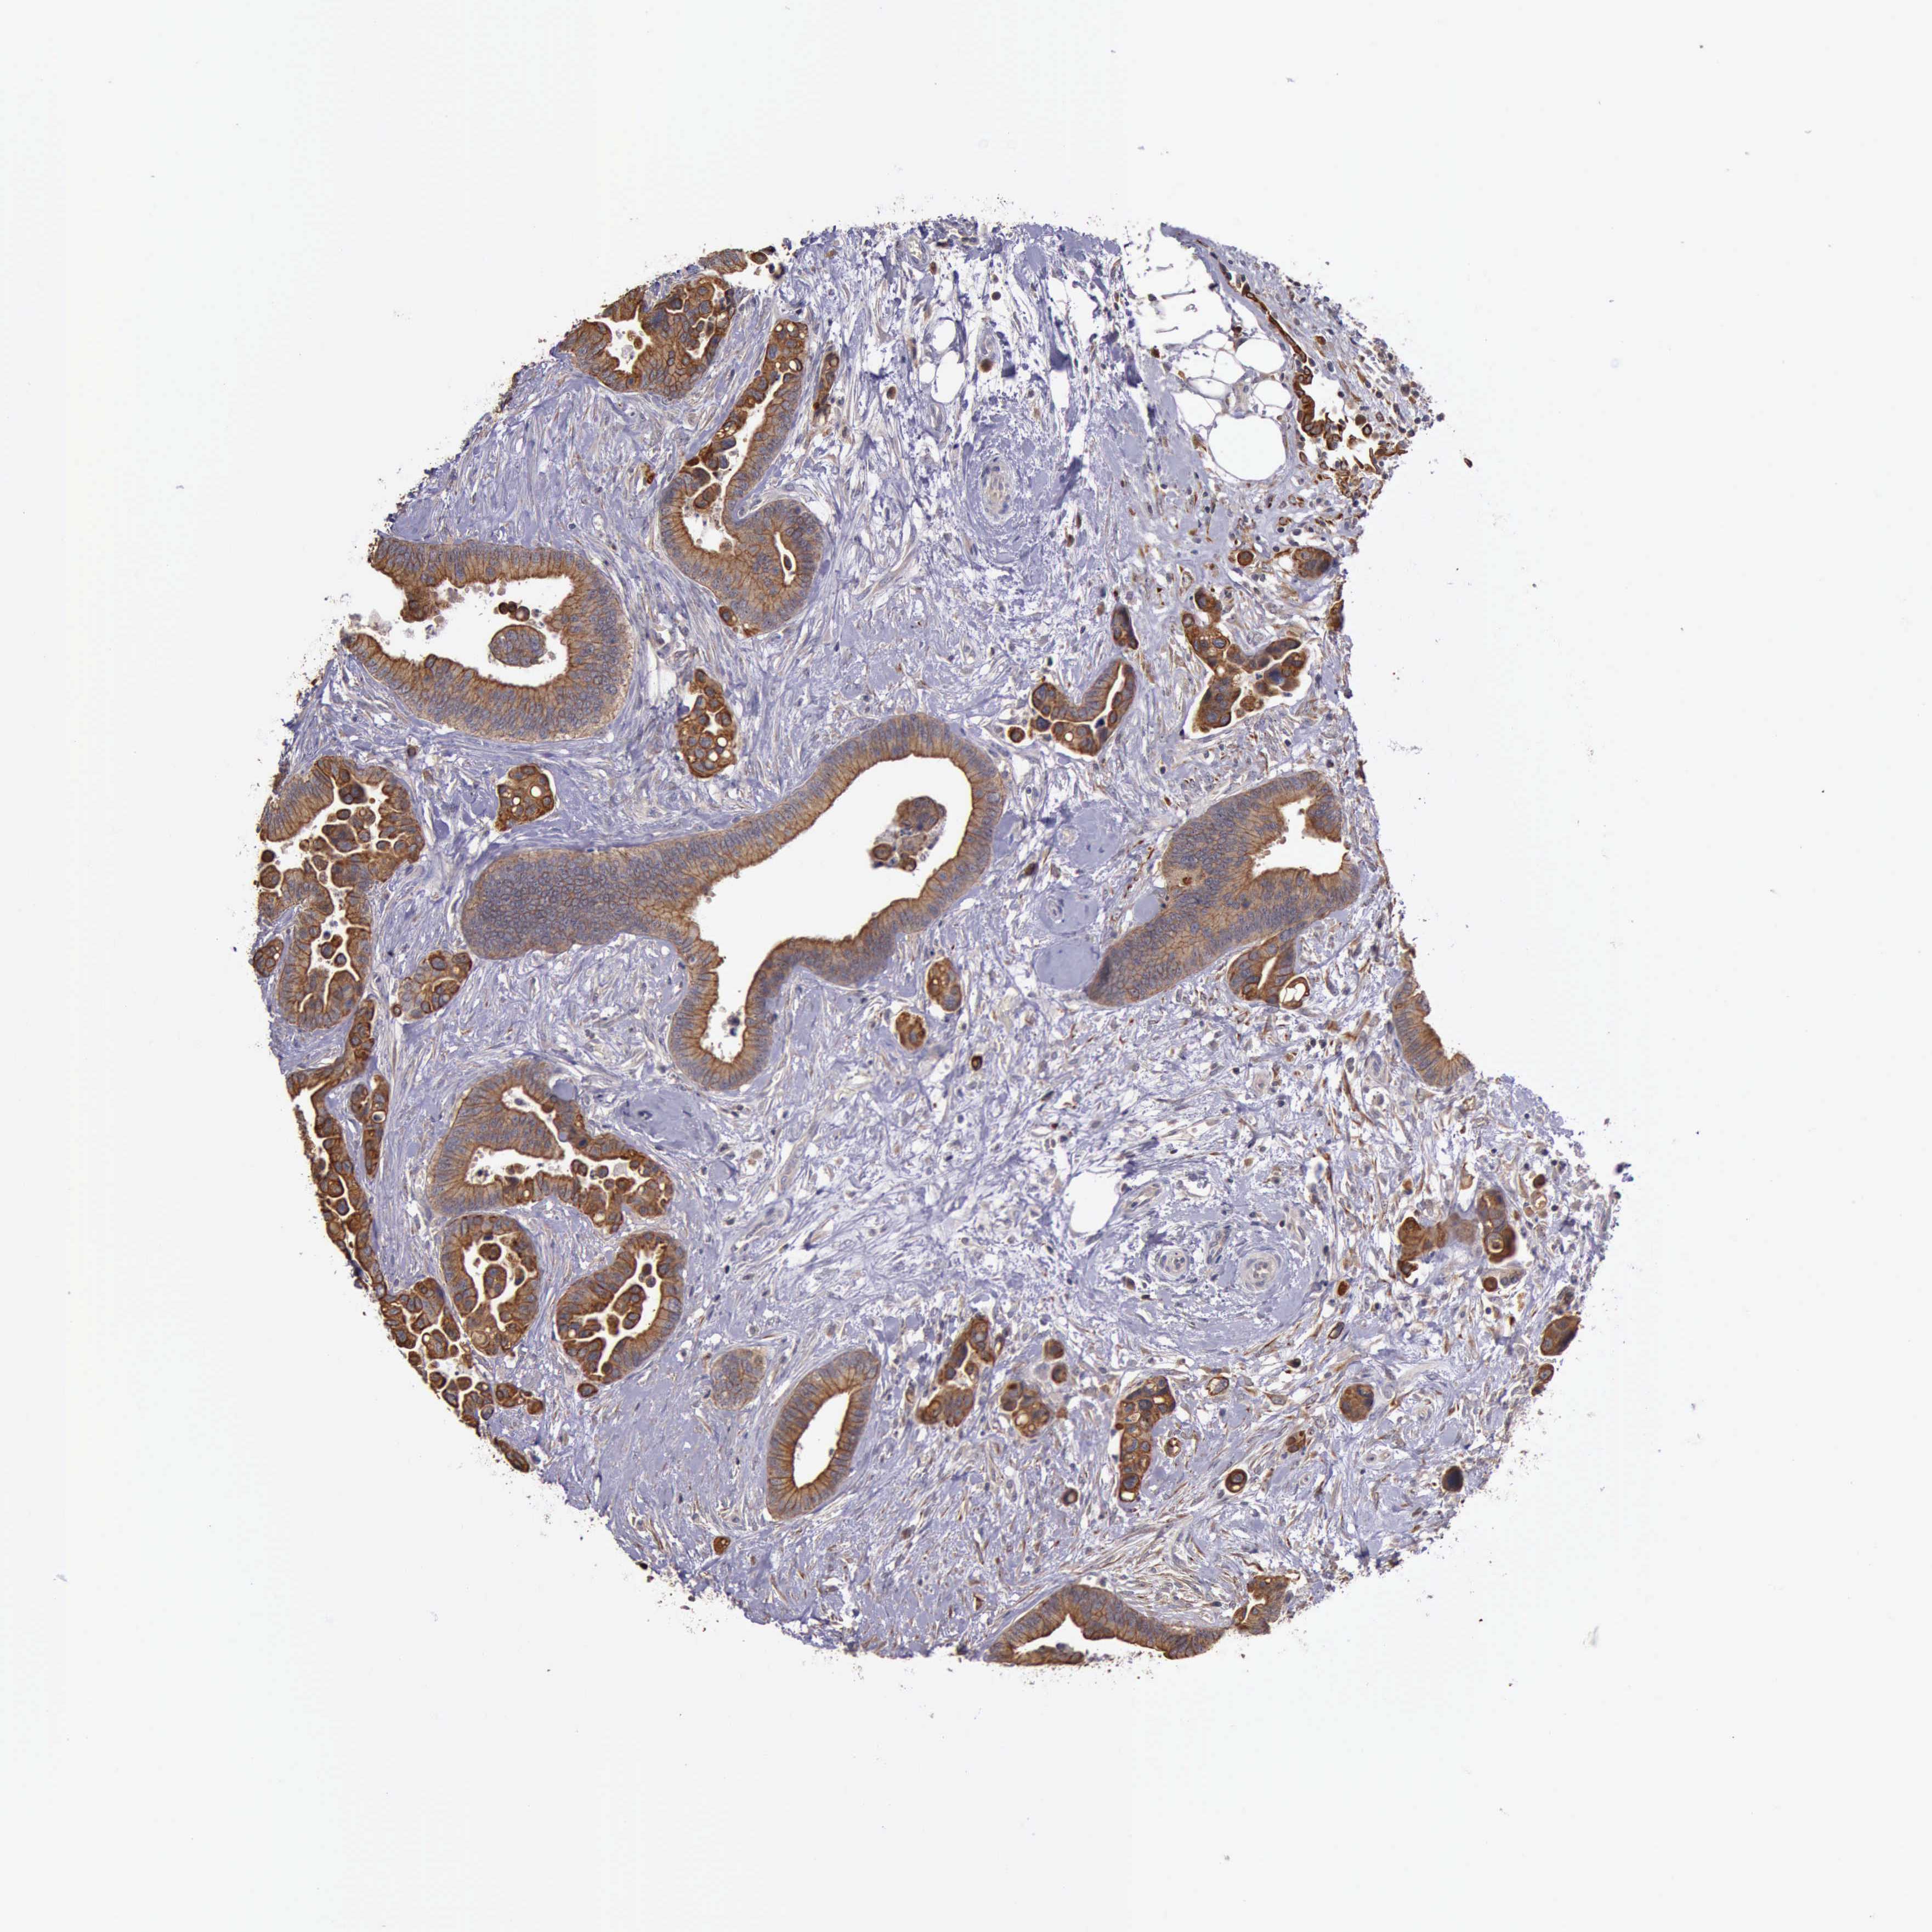

CANCER COLORECTAL CANCER Show tissue menu

Colorectal cancer

Human cancer